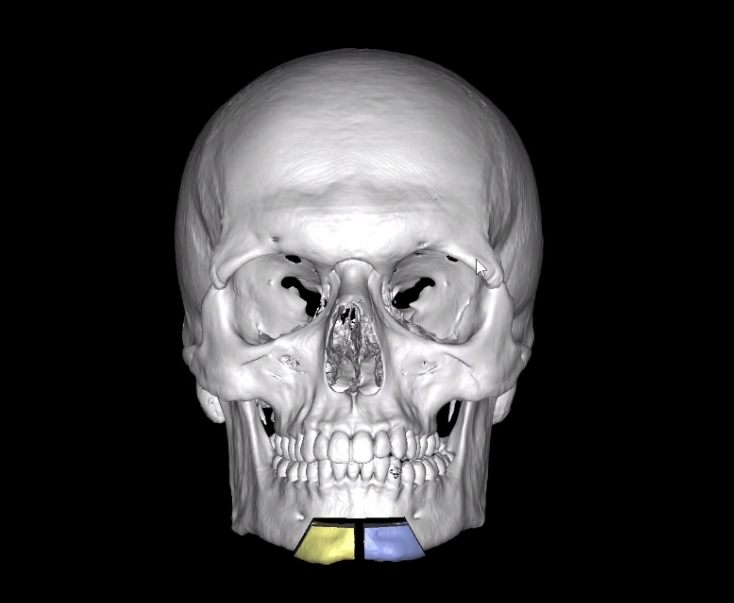

Here are my current CT Scans:

Here are my current CT Scans: